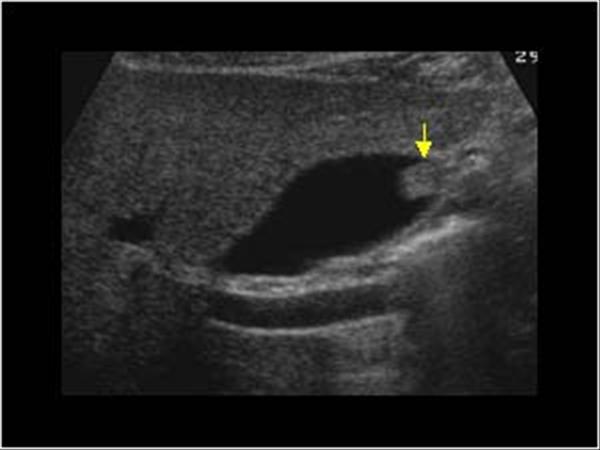

胆囊B超

胆囊B超,胆囊

b超

胆囊蛔虫死体b超图片